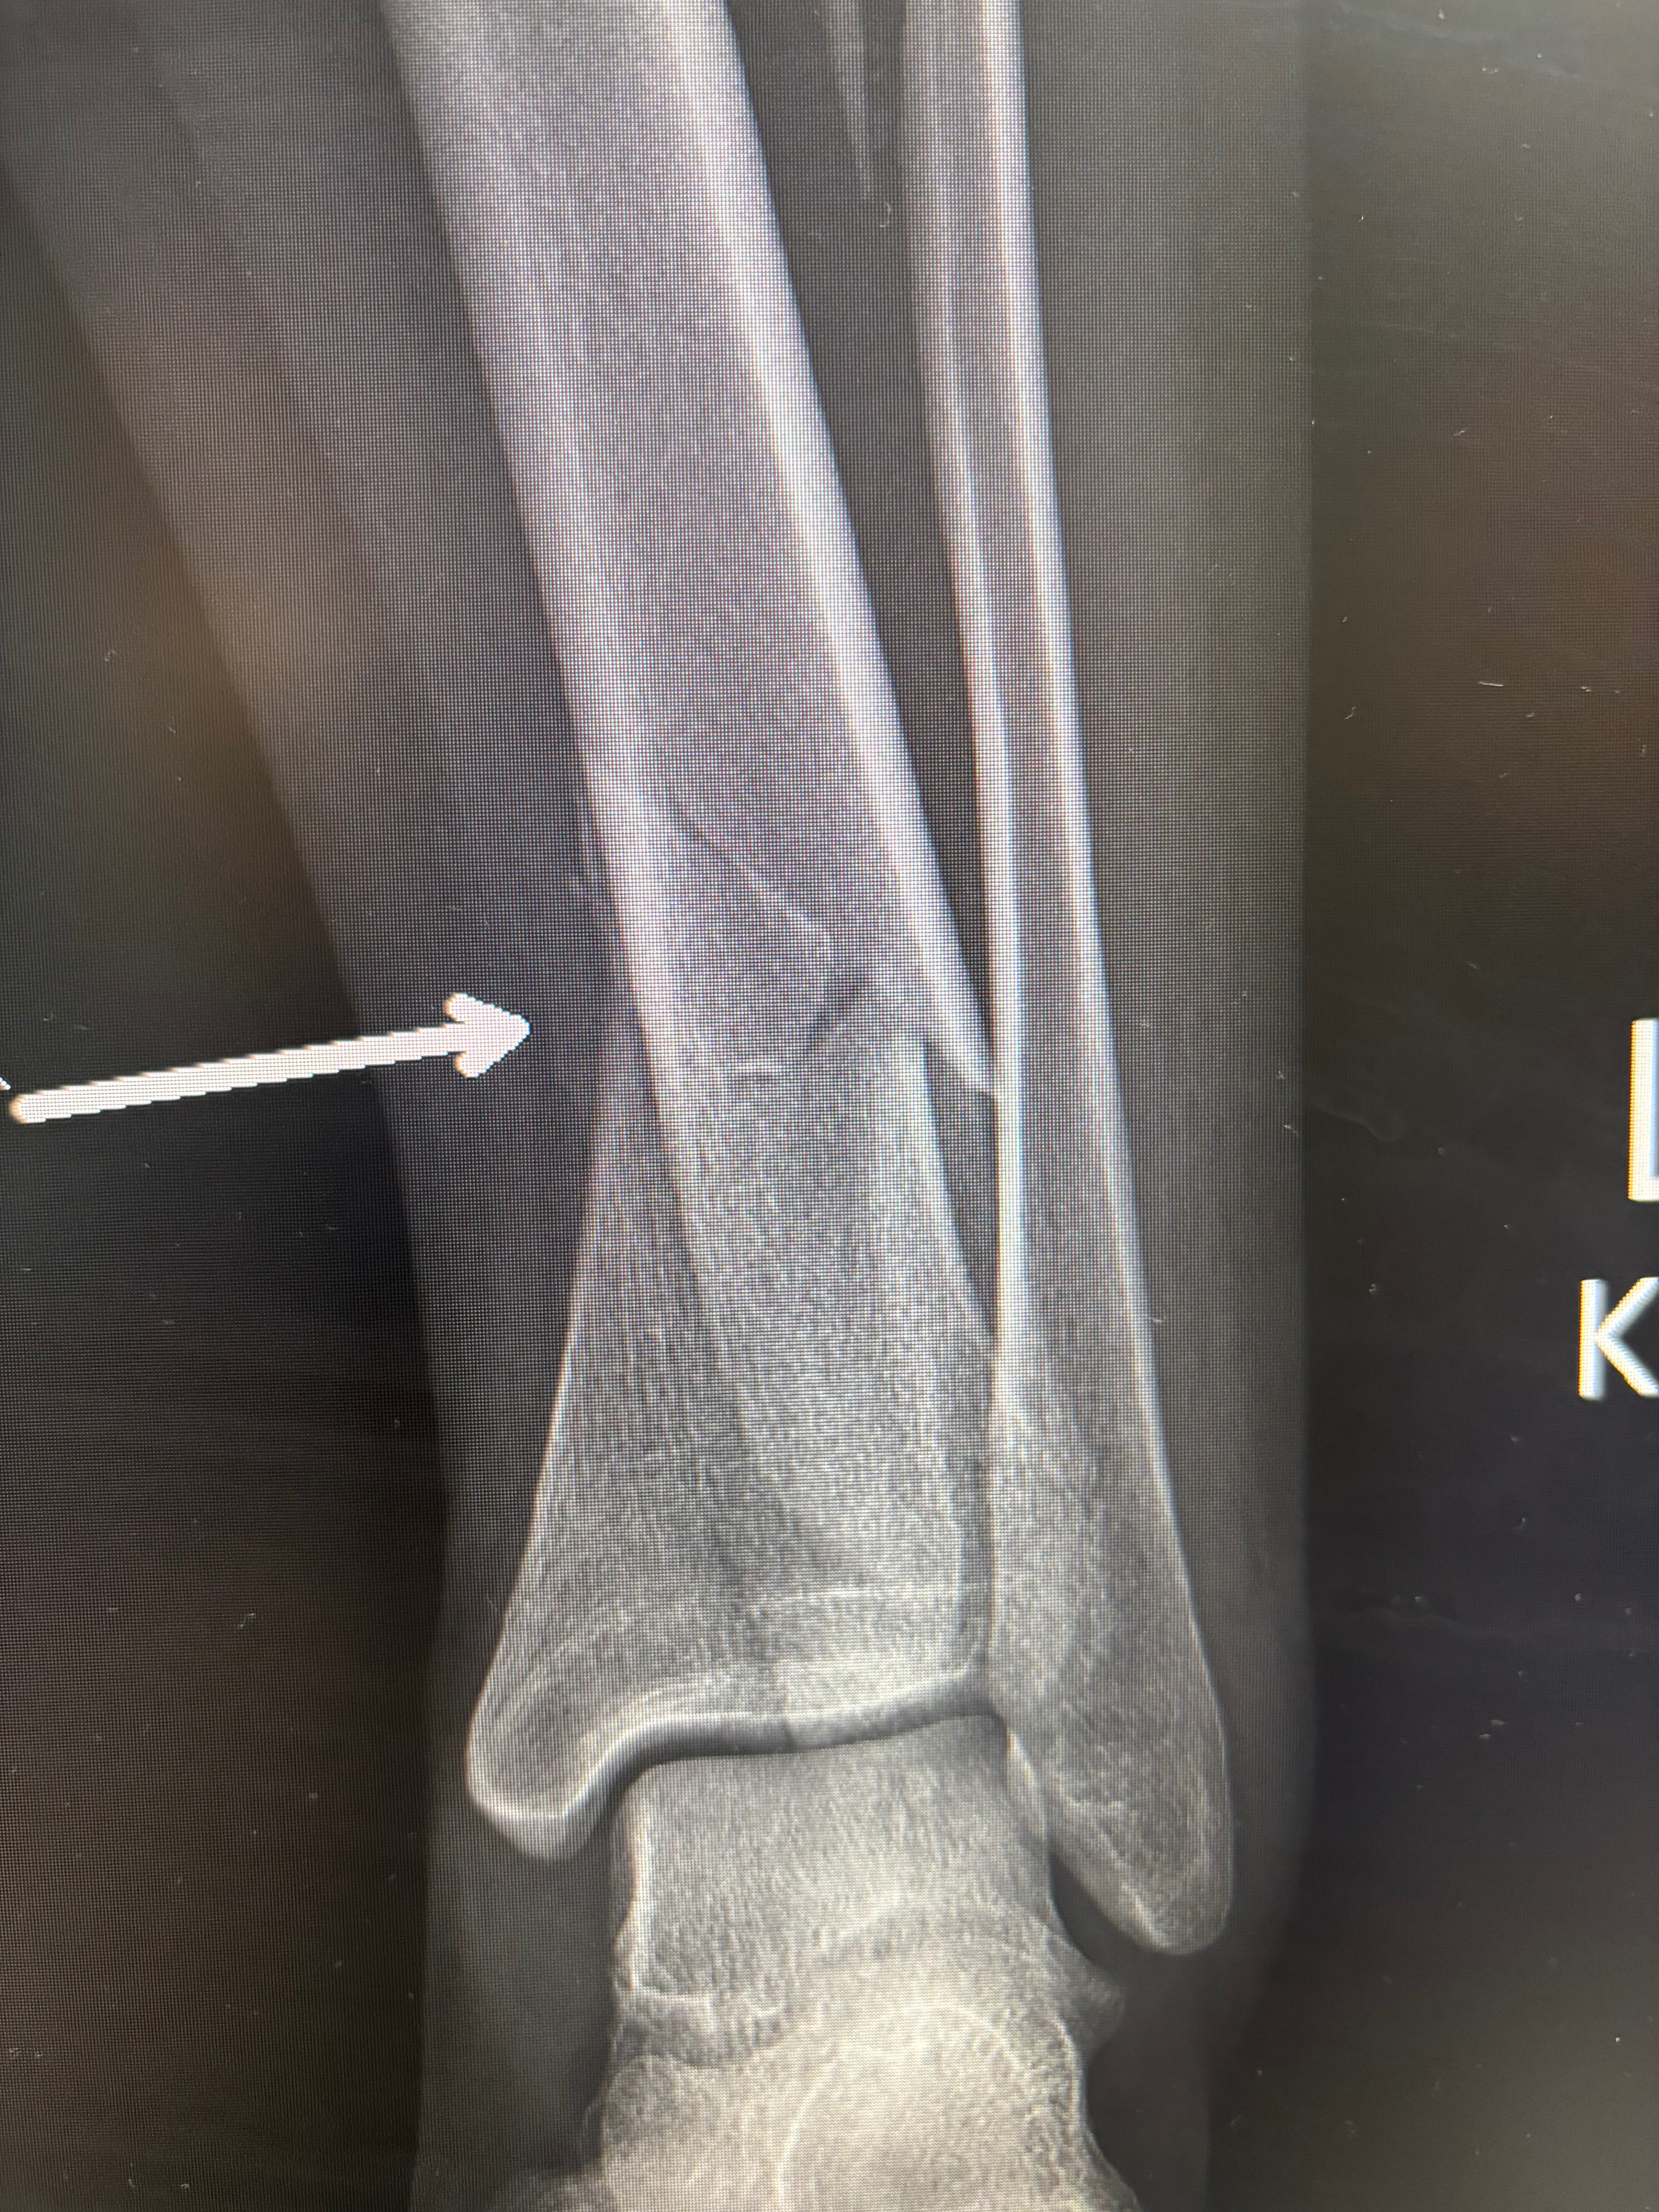

Our dear friend and coworker Kylie recently experienced a life-changing accident that resulted in a compound fracture of her tibia and fibula while riding an electric skateboard. What was supposed to be a fun day quickly turned into a painful and unexpected emergency.